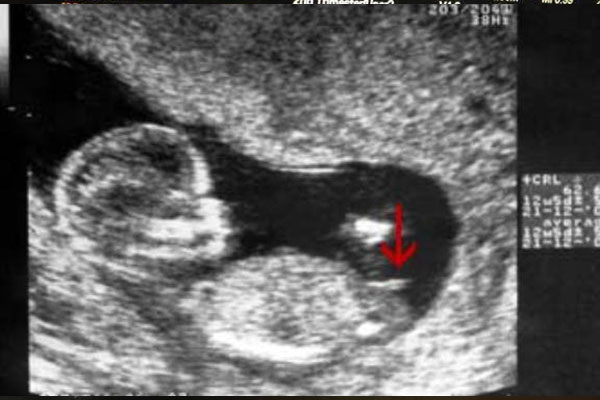

就对于nt图中的nub点,相信不少人对此都不是很了解。nt单子看男孩女孩这个方法虽然很流行,但是大多都只是对照其nt值和nt图,对nub点都不是太熟悉。据了解,通过nub点分辨男孩女孩在国外很流行,好多医生都是根据这个点组判断的。但是在国内的nt图中,胎儿下半身其实相对来说都比较模糊,腿都不好区分出来,更何况是nub点了,其实大家不妨看看这个位置。

那么nub点怎么看呢?据说是看胎儿的小屁屁和大腿根这里,如果这个位置有一个凸出来的小尖尖,那就是nub点了。根据不少已生宝妈的经验表明,一般只有男孩才会有这个点,nub点其实就是我们说的生殖器结节,男孩的生殖器一般都是往外长下来的。所以说,这是一个很明显的分辨男孩女孩的标志。

而胎儿宝宝的腿部就更好区别了,看nt图中胎儿侧面图,一般双腿都会往上翘的,好多人说腿上翘的话一般怀男孩,其实没有这样的说法,这是没有科学依据的。在nt检查中,不管男孩还是女孩,腿部这里都会有可能上翘,因为位置的原因,有的截图还看不出来腿部,这都是很正常的。